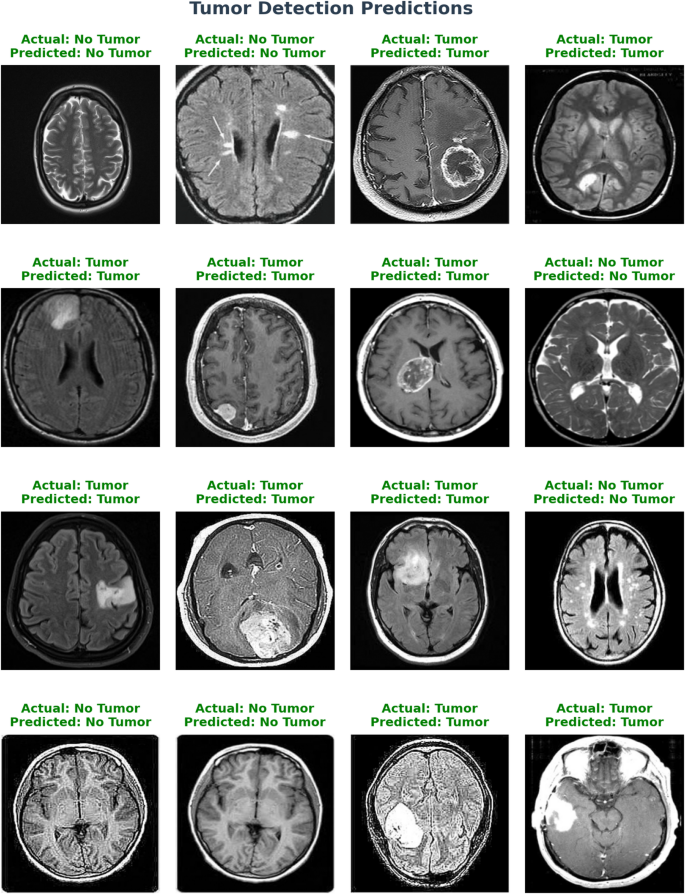

Using Xception architecture in conjunction with a transfer learning layer, a classification model shows the cancer detection performance in Fig. 10—a collection of qualitative data. Grid displays from MRI brain images, each annotated to illustrate the ground truth diagnosis with the model’s forecast. Featuring a transfer learning layer and the Xception architecture, Model 4’s classification report shows the encouraging efficiency of this method for binary medical picture classification problems. Key measures of a classification model’s performance include recall, precision, and F1-score [Table 7]. While avoiding false positives, accuracy evaluates the model’s capacity to accurately detect pertinent events. Recall finds all relevant events, therefore helping to minimise false negatives in the model. Combining accuracy and recall, the F1-score provides a harmonic mean of these two measures.

Tumor detection prediction.

Brain tumor prediction confidence result.